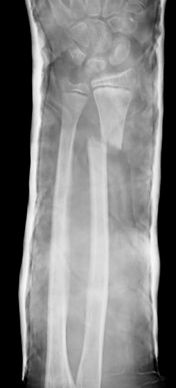

Las fracturas de ambos huesos del antebrazo al mismo nivel, con líneas de fractura oblicua-transversa o desplazamiento convergente son inestables y precisarán de tratamiento quirúrgico. En estos casos está indicado, dependiendo de la edad del paciente, el tratamiento mediante reducción y osteosíntesis. El enclavado intramedular elástico es el tratamiento de elección (Figura 15).

Figura 15: a-Imagen clínica de fractura de antebrazo derecho con gran deformidad. b- Radiografía donde se aprecia fractura de radio-cúbito de trazo transverso en el mismo nivel. c, d-Enclavado intramedular elástico. e,f- Imagen final con buena consolidación ósea.